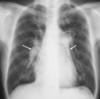

COVID-19 con patrón de vidrios despulido

COVID-19 con patrón en vidrio despulido

Vidrio despulido